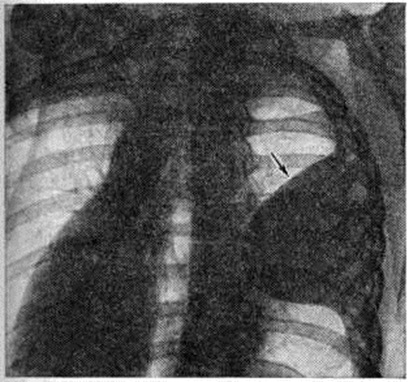

При накоплении больших количеств жидкости, когда последняя не умещается между висцеральной и диафрагмальной плеврой, она переходит в плевральные синусы. В этих случаях количество жидкости в плевральной полости обычно превышает 500 миллилитров чем выше расположена граница выпота, тем это количество больше. При переводе больного в горизонтальное положение жидкость растекается и прозрачность соответствующего лёгочного поля представляется пониженной, это так называемый феномен Ленка (смотри полный свод знаний Ленка феномен). Однако при небольшом количестве жидкости (менее 400 миллилитров) перевод больного в горизонтальное положение на трохоскопе не всегда позволяет получить положительный феномен Ленка, так как толщина слоя жидкости, растекающейся вдоль всей задней стенки грудной клетки, бывает недостаточной для того, чтобы появилась разница в прозрачности лёгочных полей. Лучшим способом выявления выпота в плевральной полости является исследование в латеропозиции на соответствующем боку. При этом жидкость растекается вдоль рёберного края, и по ширине образовавшейся пристеночной лентовидной тени можно судить о количестве выпота (рисунок 3). Если жидкости мало, целесообразно производить снимок в фазе выдоха; при этом полоска затемнения становится шире вследствие подъёма купола диафрагмы. Накопление очень большого количества жидкости в плевральной полости приводит к массивному затемнению всего лёгочного поля («тотальный плеврит») и резкому смещению срединной тени в противоположную сторону (рисунок 4).

Рис. 4.

Прямая рентгенограмма грудной клетки больного с массивным (тотальным) плевритом: выпот, заполняющий правую плевральную полость, затемняет все правое легочное поле и оттесняет органы средостения влево.